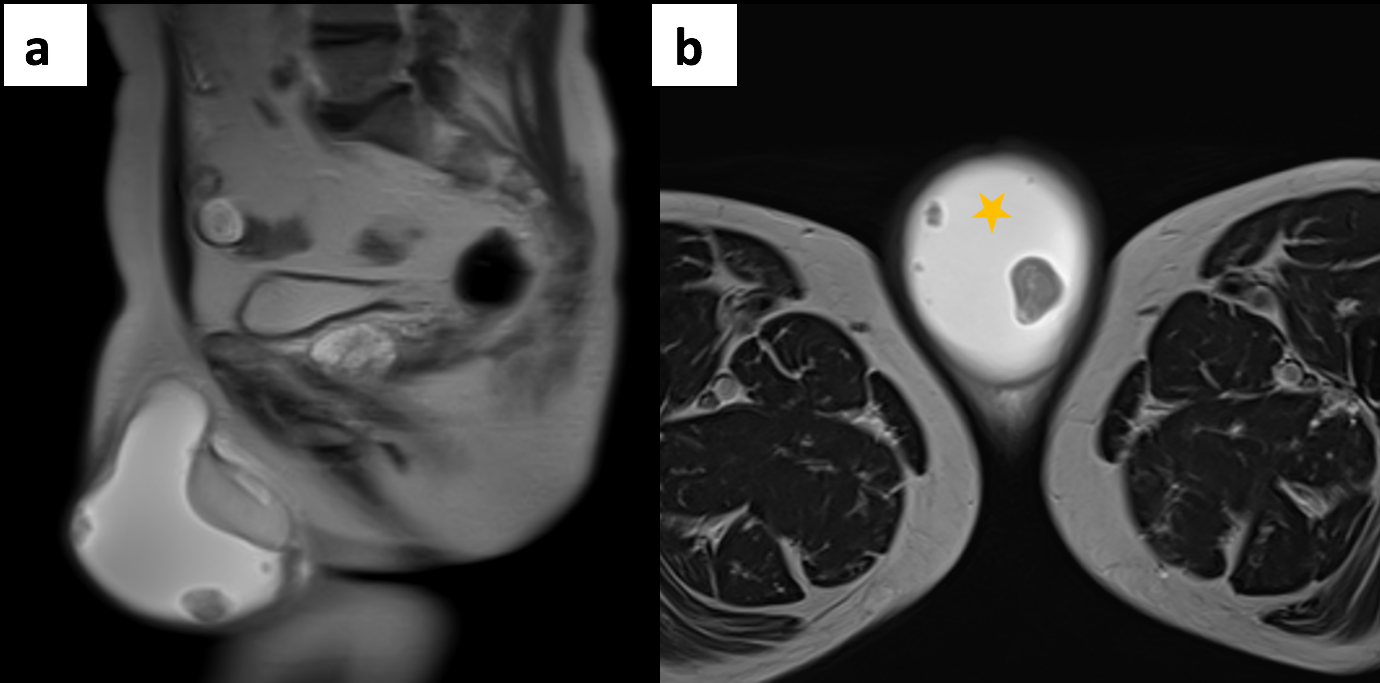

The ultrasound scan revealed turbid fluid with internal echoes and multiple hypoechoic, nodular, excrescences/adherent lesions on the tunica vaginalis. MRI scan was unremarkable.

Ultrasound is the primary imaging modality used to assess scrotal swelling or potential tumours. This is due to its easy availability, use of non-ionising radiation, cost-effectiveness and real-time features. However, ultrasound is highly operator-dependent and, therefore, requires adequate training. Other modalities, such as magnetic resonance imaging (MRI) or computed tomography (CT), can be considered when ultrasound findings are equivocal. Histology analysis of surgically removed (or biopsied) scrotal tumours is the gold standard for diagnosis. Although rare, tumours of the tunica vaginalis include fibrous pseudotumours and malignant mesotheliomas. They both primarily affect middle-aged men and are characterised by painless nodules and scrotal enlargement. The common sonographic appearance suggestive of MMTV includes the presence of singular or multiple painless nodules/excrescences in the tunica vaginalis with hydrocele. The diagnosis in this case was confirmed through orchiectomy followed by histopathology and immunochemistry.

In cases of pleural mesothelioma, ultrasound-guided percutaneous needle biopsy has shown high sensitivity (83.39%) and specificity (100%) for diagnosing malignant mesothelioma. Based on the findings from pleural mesothelioma and general imaging principles, ultrasound is highly sensitive but has limited specificity. Therefore, the authors recommend that sonographers could receive adequate training to enhance or advance their practice in fine needle aspiration cytology and ultrasound-guided biopsy of nodules of the tunica vaginalis within a one-stop rapid-access clinic to expedite the diagnosis of MMTV. This will ensure the collection of comprehensive epidemiological data and contribute to the standardisation of diagnostic and treatment protocols for MMTV. Conversely, the sensitivity and specificity of CT and MRI in diagnosing malignant mesothelioma of the tunica vaginalis have not been well established. However, CT and MRI offer complementary advantages in staging and assessing local invasion. Further research is needed to determine the diagnostic accuracy of these modalities, specifically for MMTV.